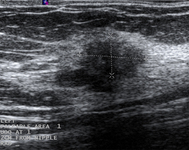

Imagen en ultrasonografía de un carcinoma invasivo

Cortesía del Dr. Lane Roland, University of Louisville; utilizada con autorización

Ver esta imagen en el contexto de la/s siguiente/s sección/es: